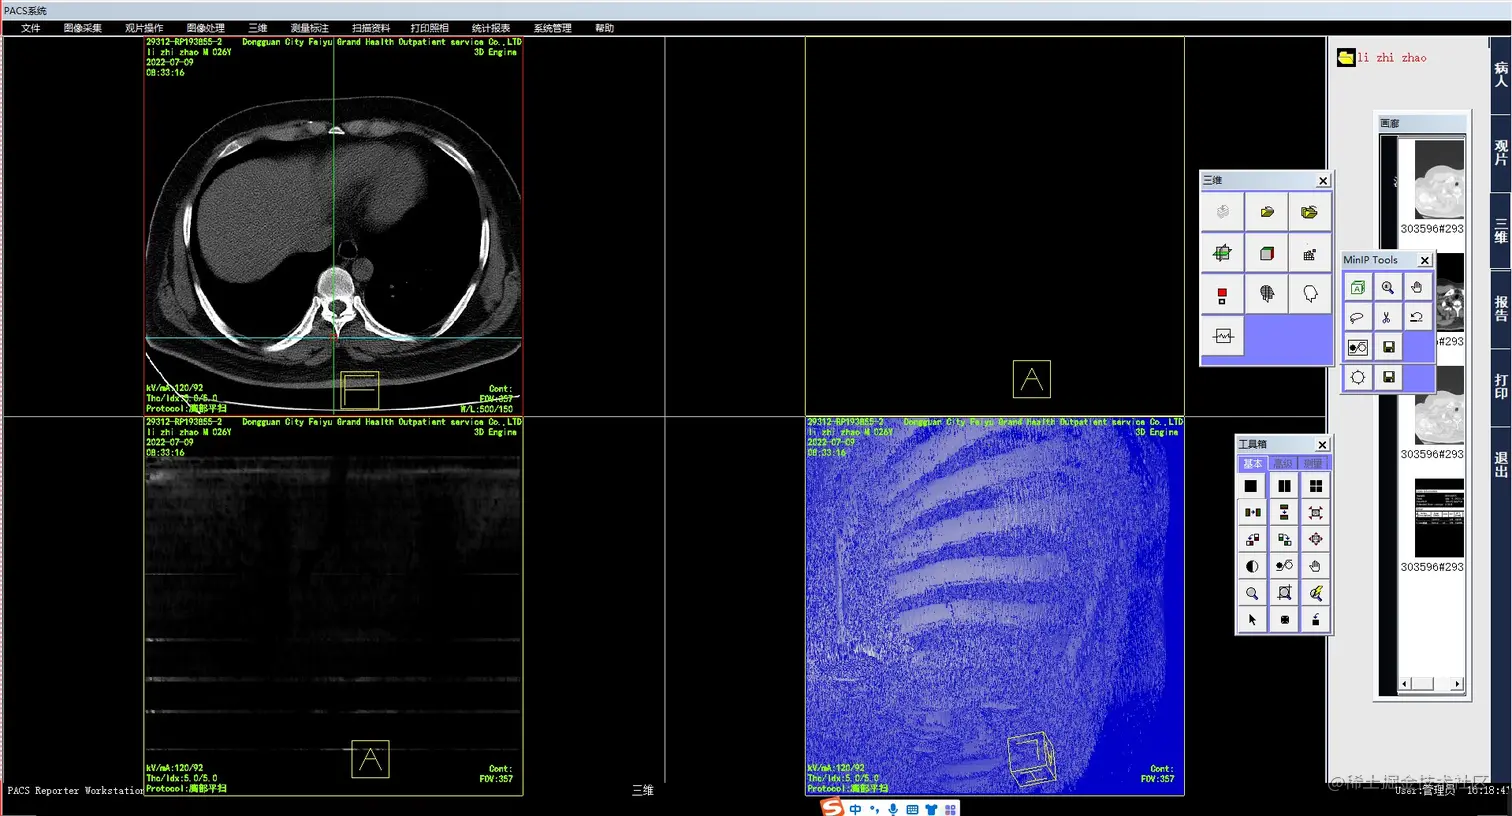

5.png 3、MinIP    MinIP(Minimum Intensity Projection),最小密度投影。和MIP正好相反,它是在某一平面方向上对所 选取的三维组织层块中的最小密度进行投影,主要用于气道的显示。偶尔也用于肝脏增强后肝内扩张胆管的显示。

4.png 4、SSD    SSD(Surface Shaded Display),表面阴影遮盖,是将操作者的眼睛作为假设光源方向,投射到CT值在设定阈值以上的体素上则不再透过继续成像,仅呈现所有表面体素的集合立体图形,适用于显示CT值与其他结构相差较大的组织结构成像。简而言之,SSD图像就像是黑白的塑形图像,所以临床上主要用于显示骨骼病变或是结肠CT重建。